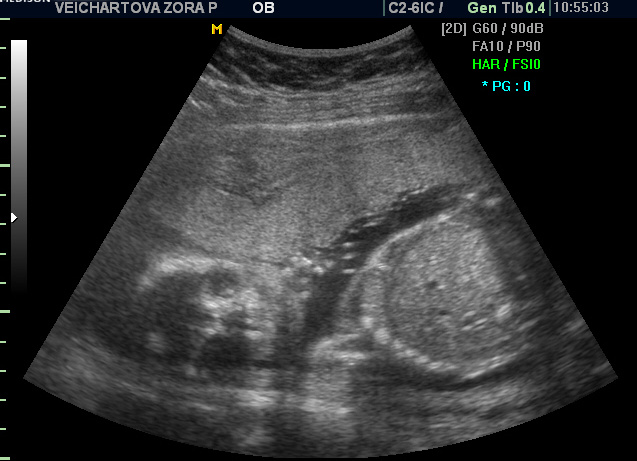

posílám dvě fotečky a snad to - zkušené maminky - poznáte ;-)

Zorko, jelikož tam nevidím vůbec nic, tedy myslím žádné varlátka, tak to vypadá na holku

. Nebo nejsem zkušená maminka

Holkaaaaa ...

To je super, ze vam to vyslo!! Tedy snad se nepletu, ale tam ten pindik proste neni;-) A jsem rada, ze je vse v poradku.... tedy ja snad budu mit dva kluky sama

Teri, on se zas nějaký klučík narodí :-) taky jsem čučela jak puk! Posledně na tom samém místě- to není holčička, a dneska naopak :-) Teri, já si fakt myslela, že je tam kluk a pořád tomu nevěřím na 100%, ten první kluk byl přece jen jasný :-))) ale doktorka je zkušená a říkala mi 99,9% holka. No téééda :-) Erik dnes přes den nespal a tak aspoň večer vytuhl chvilenku po osmé :-)